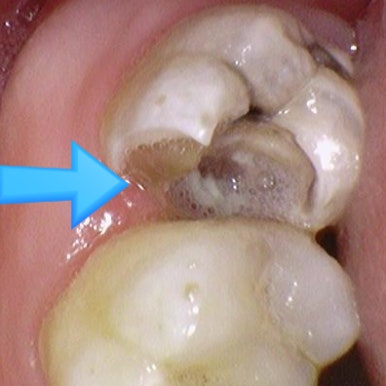

충치가 있다고 진단받았으나 겉에서 보이지 않는다고 방치하여

깨져서 온 사례

위 엑스레이 사진은 처음 방문하였을 때 엑스레이 사진입니다.

충치가 매우 심해 신경치료 해야 한다고 설명하였으나

환자분은 치아사진을 보면 치아가 썩은 것처럼 보이지 않는다면서(화살표 부분)

방치하다가 6개월이 지난 후 치아가 깨져서 오게 되었습니다.

이미 엑스레이 사진에서 충치가 매우 심함을 알 수 있고

치아 겉부분은 아주 얇게 남아있고 안은 무른 충치로 가득 차있음을 예상할 수 있습니다.